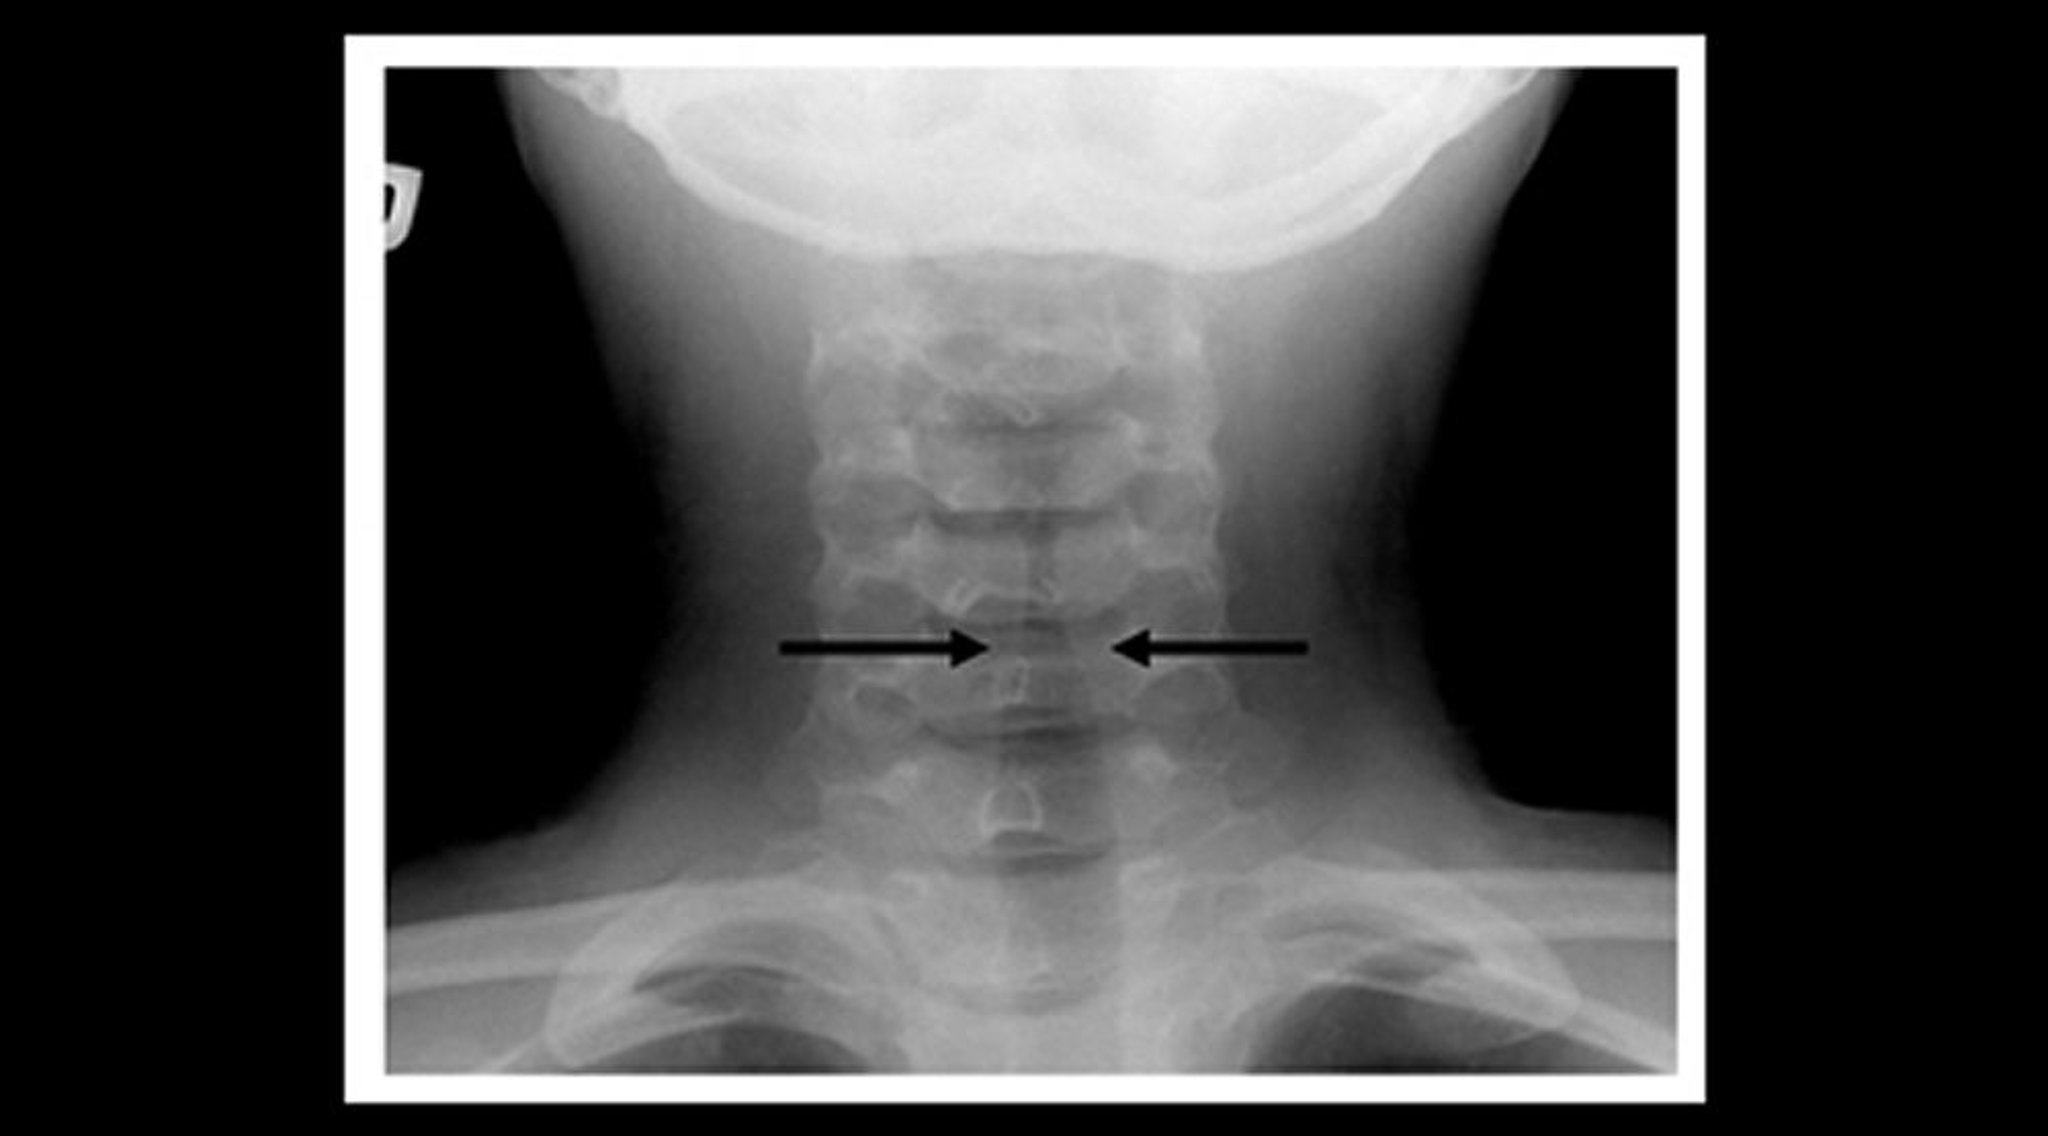

RX di un bambino con laringotracheobronchite acuta (vista coronale)

La RX del collo dei tessuti molli di un bambino con croup mostra un graduale restringimento dell'ombra sottoglottica dell'aria tracheale (segno della guglia, frecce) e la dilatazione degli spazi aerei faringei.

Image courtesy of John McBride, MD.